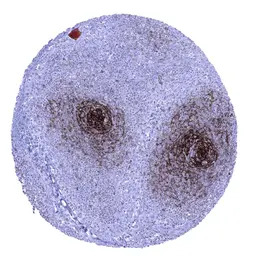

IHC-P analysis of human lymph node tissue section using GTX04472 CD23 antibody [MSVA-023M] HistoMAX.

In lymph nodes a strong CD23 immunostaining is seen in follicular dendritic cells of germinal centres while staining is moderate in follicular and perifollicular B lymphocytes.